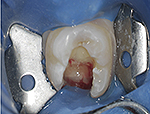

Fig. 9 The MB2 canal orifice was then exposed and a file was used to reach working length.

Figure 9

Fig. 10 This hidden MB2 canal had a separate apical exit that was prepared only after its discovery through enlarging the access opening.

Figure 10

Fig. 11 All four canals were obturated with BioCeramic Sealer and BC Coated gutta-percha cones.

Figure 11

Fig. 12 The original ultra-conservative access may have saved some tooth structure, but would have resulted in missing the MB2, which would have negatively affected the case outcome postoperatively due to its separate apical exit.

Figure 12